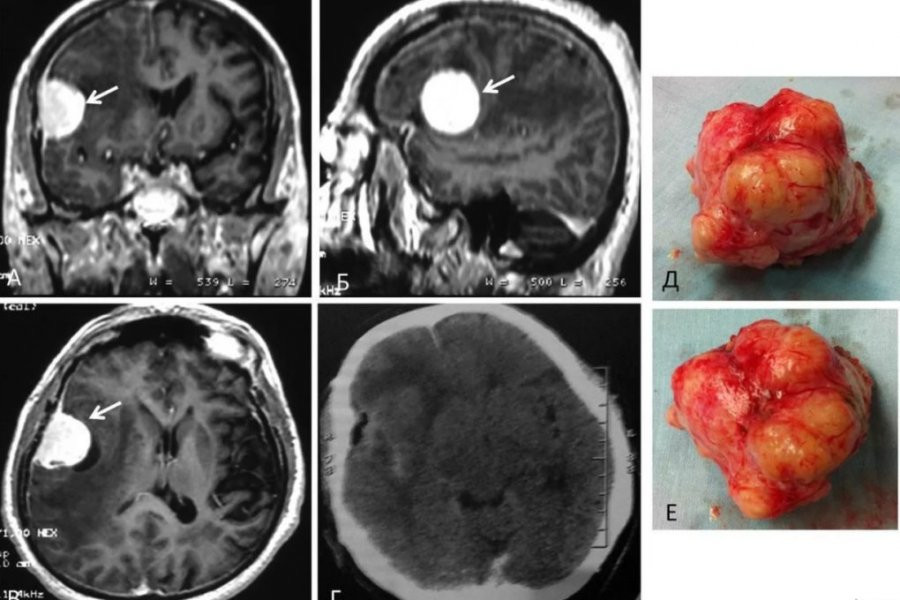

Обследования показало, что у Хэмптона образовалась в мозге злокачественная опухоль - глиобластома, которая является агрессивной формой рака. Это заболевание и оказало влияние на его характер. Мужчине была проведена операция, и его поведение вернулось в норму. Сейчас Хэмптон проходит химиотерапию.